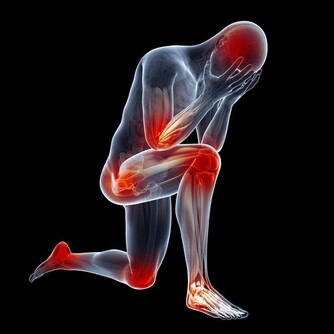

01.腿腳要求減負擔

腿腳是骨骼、肌肉、關節形成的“鐵三角”,幾乎承載著身體的整個重量,僅膝蓋就承受9倍於體重的壓力。

腿腳還是交通樞紐,佈滿了人體50%的神經、50%的血管,流淌著50%的血液。

負擔過重、行動姿勢不當、寒氣侵入等都會讓腿腳受傷。另外,腿腳最容易受到傷害的地方是關節。